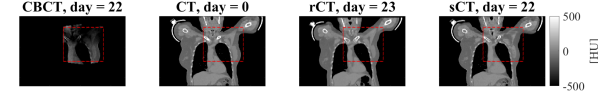

Figure 3, 4, 5 show examples of CBCT and sCT obtained from the single network for a HN, breast and lung cancer patient, respectively. One can observe that the network reduced scatter artefacts while retaining anatomical accuracy. Considering an example of lung patient (Figure 5), one can observe the occurrence of atelectasis between CT and rCT/sCT.

Figure 4: Coronal views for the breast cancer patient B27 of: (1stst{}^{\textrm{st}} row) CBCT (1stst{}^{\textrm{st}} column), CT (2ndnd{}^{\textrm{nd}} column), rescan CT (rCT, 3rdrd{}^{\textrm{rd}} column) and synthetic CT (sCT, 4thth{}^{\textrm{th}} column), along with (2ndnd{}^{\textrm{nd}} row) the respective difference to rCT, the doses (3rdrd{}^{\textrm{rd}} row). The red, black, or green dotted rectangles indicate the position of MaskCBCTCBCT{}_{\textrm{\tiny CBCT}}. The days refer to the acquisition date of the rCT. In the 4thth{}^{\textrm{th}} rows, the DVH is shown for target and OARs of sCT (continuous lines) and rCT (dashed lines).